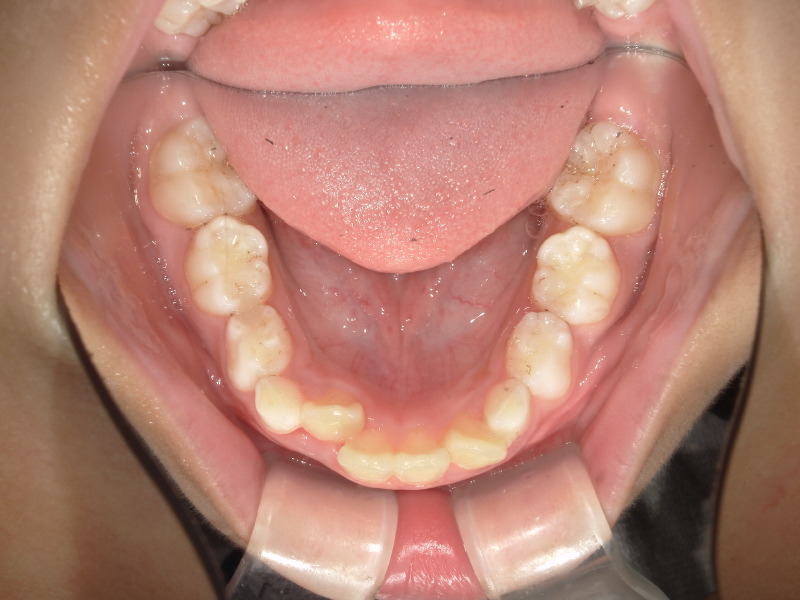

下の歯並びは2番目の歯が後ろから生えてきており、スペースが足りないようでした。

噛み合わせも少し変化があったり下の歯も並ぼうとはしていますがまだスペースは足りず入れませんでした。

3番目の歯が抜けて生え変わる頃にグッと噛み合わせが変化して、下の歯も並びました。